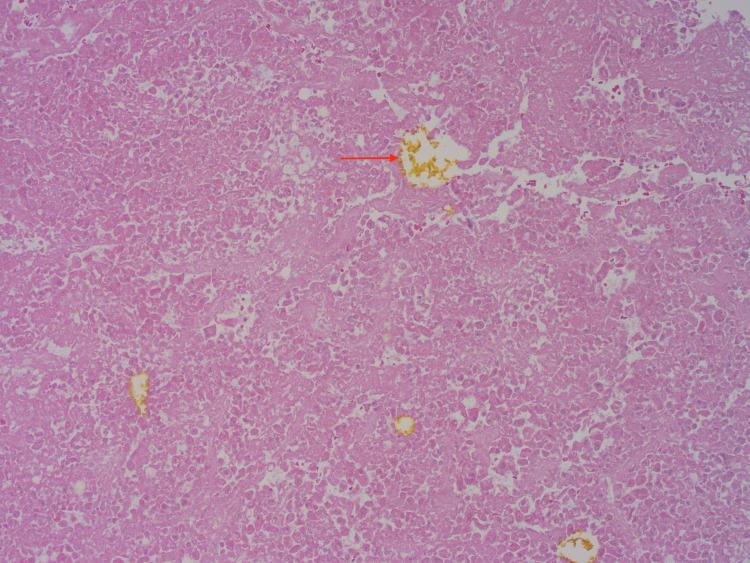

Hepatocellular carcinoma (HCC) is a complication of end stage liver disease. Even rarer is right atrial tumor thrombus burden due to HCC. Common metastatic sites of HCC in descending order are lung, peritoneum, and bone. We present a patient with liver cirrhosis due to nonalcoholic fatty liver disease (NAFLD) admitted due to incidental finding of right atrial thrombus on echocardiography after missing HCC surveillance for four years. Patient received a computed tomography (CT) scan that showed an inconclusive liver lesion despite two liver biopsies, and patient was incidentally found to have clear cell HCC diagnosed after right hepatectomy. Right atrial thrombus was treated with surgical thrombectomy and pathology showed necrotic HCC thrombi in right atrium with bile pigment. Due to the possibility of tumor growth with extrahepatic manifestations, screening in compensated cirrhosis is essential.

摘要

肝细胞癌(HCC)是终末期肝病的一种并发症。因HCC导致右心房肿瘤血栓负荷的情况更为罕见。HCC常见的转移部位依次为肺、腹膜和骨。我们报告一例因非酒精性脂肪性肝病(NAFLD)导致肝硬化的患者,该患者在漏查HCC四年后,因超声心动图偶然发现右心房血栓而入院。患者接受了计算机断层扫描(CT),尽管进行了两次肝脏活检,但肝脏病变仍不明确,患者在右肝切除术后偶然被诊断为透明细胞HCC。右心房血栓通过手术取栓治疗,病理显示右心房有坏死的HCC血栓伴胆色素。由于肿瘤有肝外表现生长的可能性,对代偿期肝硬化患者进行筛查至关重要。